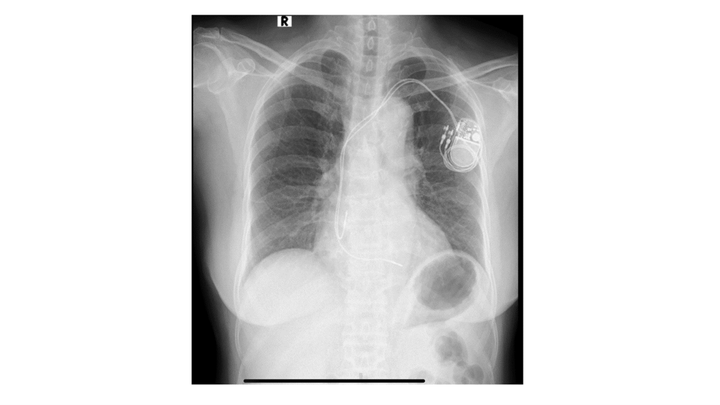

Hình ảnh một ca điều trị rối loạn nhịp tim hiệu quả bằng giải pháp ít xâm lấn cho bệnh nhân nữ 75 tuổi. (Ảnh: Thuỳ Dương)

Trong đó, giải pháp tiên tiến nhất hiện nay là sử dụng máy tạo nhịp tim và máy khử rung tim. Đây là những thiết bị y học hiện đại, nhỏ gọn, mang lại hiệu quả vượt trội trong việc điều trị các rối loạn nhịp tim nghiêm trọng.

Máy tạo nhịp tim giúp điều chỉnh nhịp tim ổn định bằng cách gửi các xung điện đến các buồng tim. Tùy thuộc vào mức độ bệnh, bệnh nhân có thể được cấy máy tạo nhịp một buồng tim, hai buồng tim, hoặc máy tạo nhịp không dây. Với tuổi thọ từ 10 đến 15 năm, các thiết bị này đảm bảo người bệnh có thể duy trì cuộc sống bình thường mà không còn lo ngại các triệu chứng như ngất xỉu hay suy tim, khi hết tuổi thọ, bệnh nhân vẫn có thể được thay một máy mới.

Máy khử rung tim tự động, mặt khác, được thiết kế để ngăn ngừa đột tử do tim ngừng đập. Thiết bị này hoạt động bằng cách phát hiện các nhịp tim nguy hiểm và tạo ra một cú sốc điện nhằm khôi phục lại nhịp tim bình thường. Đây là giải pháp đặc biệt hiệu quả cho những bệnh nhân có nguy cơ cao bị đột tử do tim.